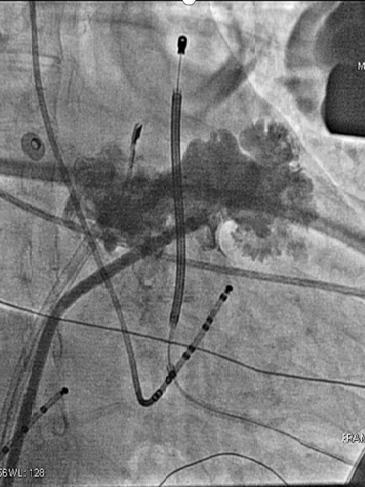

房颤导管消融术

左心耳封堵术

患者术前心电监护示房颤心律,穿刺左侧股静脉1次,经6F静脉鞘送“电生理电极导管(四极)”至右室心尖部行右心导管检查,穿刺右侧颈内静脉一次,置入6F静脉鞘,沿鞘送“电生理诊断导管(十极)”至CS,穿刺右侧股静脉2次,分别置8.5F房间隔穿刺鞘,分别使用“一次性使用房间隔穿刺针”成功穿刺房间隔成功后将房间隔穿刺鞘置入左房,分别置入“星型磁电双定位标测导管”和“诊断/消融可调弯头端导管”。Carto3 三维标测系统指导下构建左房三维电解剖图。然后按以下步骤消融:在离右侧肺静脉口0.5cm处对右侧肺静脉进行环形消融,放电设置(50瓦,冷盐水流速30ml/min),各点时间10s左右,星型磁电双定位标测导管检测,肺静脉与心房达到双向电隔离为准;同样方法对左侧肺静脉进行环形消融,星型磁电双定位标测导管检测,肺静脉与心房达到双向电隔离为准。消融后给予200J同步电复律,患者转复为窦性心律。将其中一个8.5F房间隔穿刺鞘置换为心脏超声导管至左心房,将8.5F房间隔穿刺鞘置换为封堵器专用长鞘后将猪尾导管置入左房,调整至左心耳内,行左心耳造影,测量左心耳口部最大直径35mm,左房内无血栓,DSA指导下选用左心耳封堵器LAmbre3640,置入长鞘内,在左心耳内释放成功,造影检查提示封堵器位置良好,植入器械位置正确。造影检查提示未见明显分流,经心腔内超声可见植入器械位置正常,释放封堵器。结束手术,拔除电极及鞘管,局部加压止血,安返病房,术中生命体征平稳。